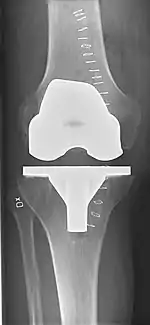

![]() |

Angles commonly measured before knee replacement surgery: |

To indicate knee replacement in case of osteoarthritis, its radiographic classification and severity of symptoms both should be substantial. Such radiography should consist of weightbearing X-rays of both knees: AP, lateral, and 30 degrees of flexion. AP and lateral views may not show joint space narrowing, but the 30-degree flexion view is most sensitive for narrowing. Full-length projections also are used in order to adjust the prosthesis to provide a neutral angle for the distal lower extremity. Two angles used for this purpose are:

- Hip-knee-shaft angle (HKS),[10] an angle formed between a line through the longitudinal axis of the femoral shaft and its mechanical axis, which is a line from the center of the femoral head to the intercondylar notch of the distal femur.[12]

- Hip-knee-ankle angle (HKA),[11] which is an angle between the femoral mechanical axis and the center of the ankle joint.[12] It is normally between 1.0° and 1.5° of varus in adults.[13]